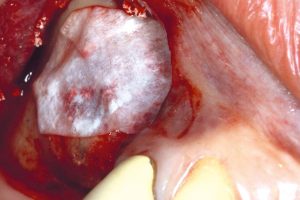

IMPLANTOLOGIE, PARODONTOLOGIE A ÚSTNÍ A CMF CHIRURGIE

- Sinus lift

- augmentace alveolu

- Intraoseální vady

- Augmentace extrakční rány

- Kostní defekty

- Furkační defekty